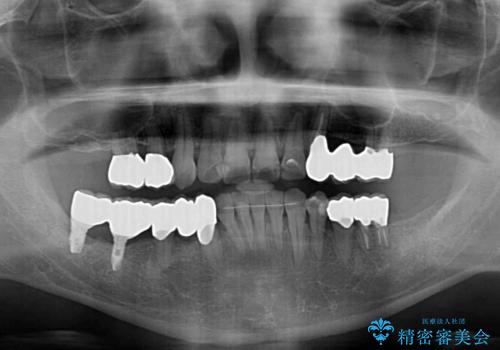

初診時に4年かかりますとお伝えし、実際に4年数ヶ月を要する治療となりました。

治療中は仮歯が頻繁に脱落したり、歯周外科によりむき出しとなった歯根が知覚過敏を起こしたりと、苦労は絶えませんでしたが、4年の治療の後にスッキリと仕上げることができました。